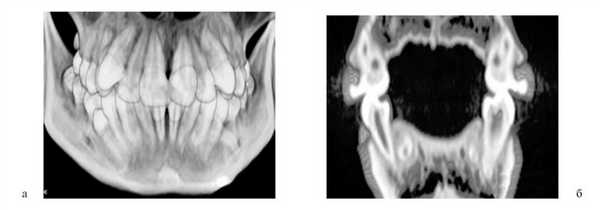

У всех обследованных выявили клиническое сужение зубных рядов и аномалии положения отдельных зубов, у 53 (42,1%) — обратную резцовую окклюзию, у 126 (100%) — деформацию окклюзионной плоскости. При анализе диагностических моделей челюстей и сопоставлении полученных результатов с показателями индивидуальной нормы у всех обследованных определялось статистически достоверное (р≤0,05) сужение зубных рядов разной степени.

У пациентов 1-й группы с односторонней расщелиной во временном прикусе расстояние между клыками ВЧ оказалось меньше нормы на 2,3±0,7 мм, между первыми молярами — на 2,1±0,6 мм. У пациентов с двусторонней расщелиной расстояние между клыками ВЧ было меньше нормы в среднем на 2,1±0,4 мм, между верхними первыми молярами — на 1,8±0,5 мм.

При измерении диагностических моделей пациентов 2-й и 3-й групп по Korkhaus обнаружено укорочение переднего отдела ВЧ на 1,7±0,5 мм (р≤0,05) у 15,5% пациентов. В то же время у 28,5% обследованных отмечали удлинение переднего отдела ВЧ на 2,5±0,3 мм (р≤0,05) и у 4,3% пациентов удлинение переднего отдела нижней челюсти на 1,5±0,4 мм (р≤0,05). При изучении гипсовых моделей челюстей методом D. Pont и сопоставлении полученных результатов с показателями индивидуальной нормы у всех обследованных установлено статистически достоверное (р≤0,05) сужение зубных рядов различной степени. Расстояние между верхними первыми премолярами было меньше нормы в среднем на 3,8±0,4 мм, между верхними первыми молярами — на 2,3±0,8 мм, между первыми нижними премолярами — на 3,6±0,7 мм, между первыми нижними молярами — на 2,7±0,8 мм. В области премоляров сужение зубных рядов составило от 1,7 до 5,3 мм, а в области моляров — от 2,6 до 7,4 мм.

У 98 (77,8%) обследованных обнаружили несимметричное смещение зубов по зубной дуге и наклон в мезиальном направлении, что приводило к уменьшению ширины зубной дуги и укорочению длины ее переднего отрезка. Такое нарушение сочеталось с сужением зубных рядов в боковых отделах у всех 126 пациентов. Для всех пациентов были характерны аномалии положения зубов на границе с расщелиной.